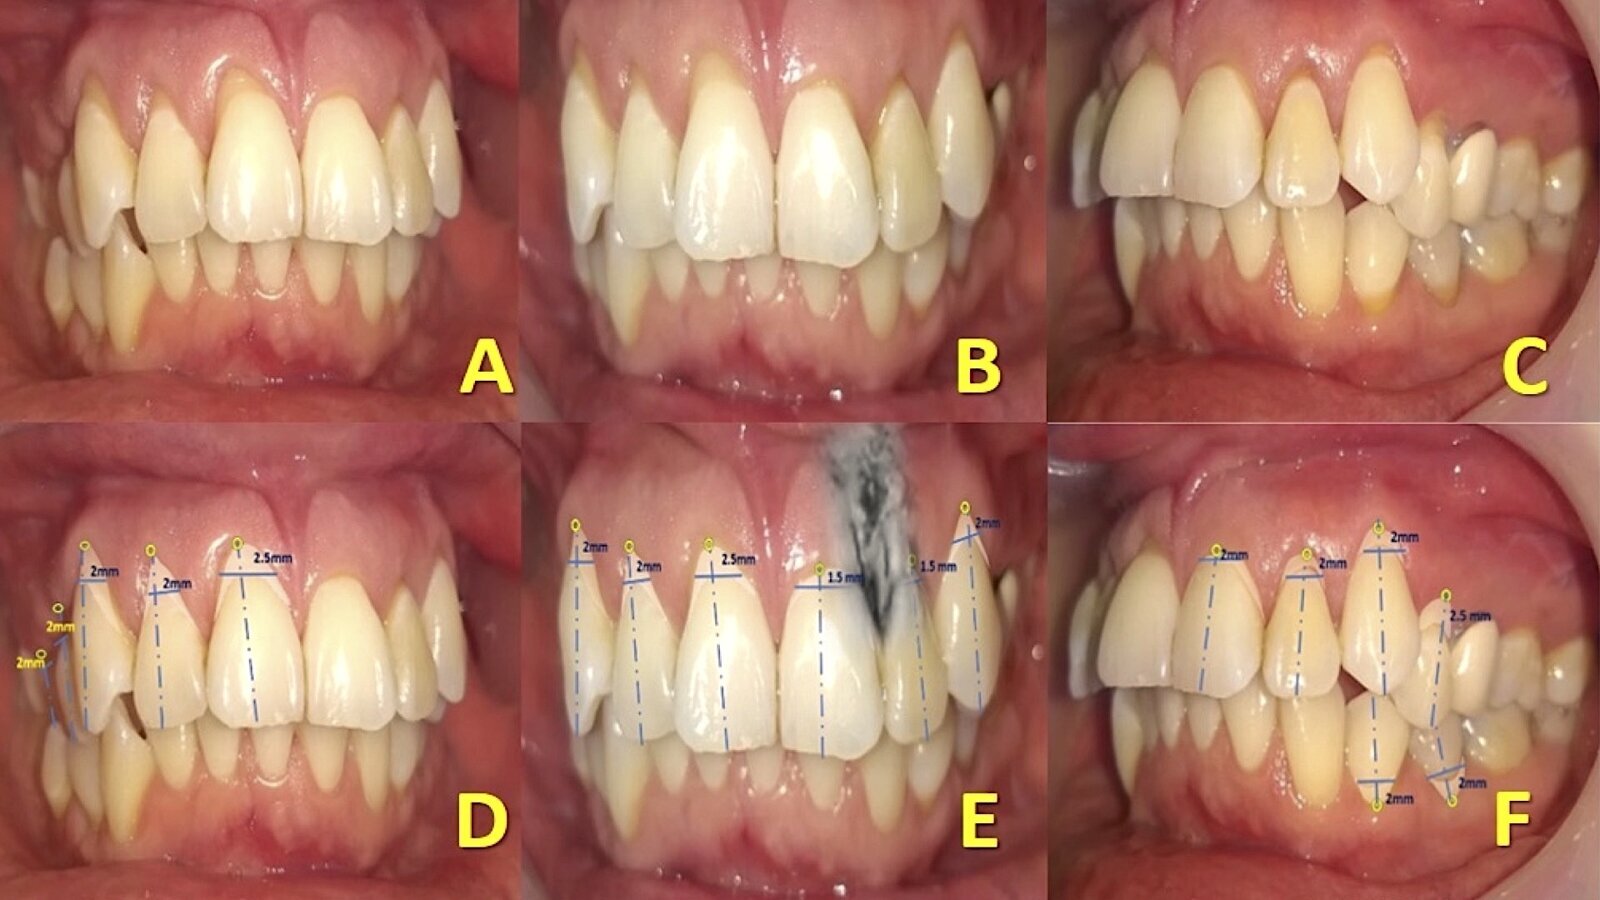

Figura 1. Fotografías iniciales del caso (A, B y C). Medición y registro de recesiones y lesiones LCNCs con sondeo (D, E y F). Evaluación de la lesión periapical en el diente 22 con superposición de aspecto tomográfico vestibular (E).

Paciente femenina de 37 años que se presentó a consulta refiriendo ligero malestar en el diente 22, posterior a un tratamiento de conductos después de 14 meses, el cual no presentaba signos inflamatorios en fondo de saco, ni fístula. Reportó además hiperestesia dentinaria en ambas arcadas tras la ingesta de alimentos atemperados y endulzados. En los datos generales de la historia clínica odontológica, manifestó no presentar antecedentes patológicos o hereditarios, no era fumadora, ni exfumadora, no bruxista; no reportó dietas con influencia de alimentos abrasivos-veganos o líquidos acidúricos, tampoco episodios de reflujo gastroesofágico3. Reportó utilizar para su higiene bucal personal cepillo de cerdas blandas (técnica de Bass), hilo dental y accesorios interproximales. A la inspección bucal armada se observaron y registraron restauraciones y prótesis con desajuste. En ambas arcadas se obserbvó una combinación masiva de recesiones y LCNCs. La inspección se complementó con sondeo periodontal y los datos de medición se agregaron en un periodontograma. El tamaño de las recesiones, el nulo sangrado al sondaje periodontal y la profundidad promedio de inserción 1 mm, nos informa de un periodonto reducido sin periodontitis (con recesiones gingivales)4.

La literatura menciona tres métodos para evaluar el grosor del fenotipo gingival de un diente defectuoso: la transparencia de la sonda dentro del surco gingival es el método más utilizado hoy en día, puesto que ha demostrado ser sencillo y eficaz para evaluar el espesor gingival5,6. Las recesiones fueron clasificadas según Miller y las LCNCs según la clasificación de Cairo7. En la interpretación radiográfica dentoalveolar del diente 22, se observó una zona radiolúcida difusa, circundante no definida, con material radiopaco extralimitando el ápice, determinando una periodontitis apical, derivada de tratamiento endodóntico deficiente, que requirió respaldo tomográfico. La paciente cooperó en todo momento y estuvo atenta para resolver este grupo de problemas que la aquejaba, señalando la preocupación por atenderlos de inmediato con expectativa positiva (Figura 1).